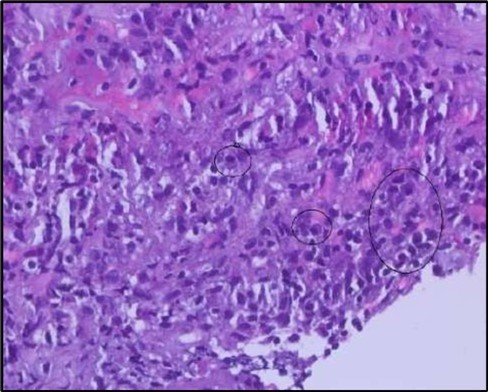

Two weeks post-surgery, the left eye showed significant healing, with a small conjunctival granuloma and vascularization at the ulcer margins. The cornea was clear with a central leading edge nasally, deep and quiet anterior chamber and clear lens. VA 6/6 bilaterally and IOP normal. Histopathology of excised conjunctiva showed non-keratinized squamous epithelium with superficial erosions, stromal elastosis, hemorrhage, and inflammatory infiltration, but no signs of granulomatous disease, malignancy, or viral evidence, findings consistent with idiopathic localized inflammatory process. The patient reported significant relief and satisfaction post-surgery, resuming normal activities. Treatment continued with oral prednisolone 25 milligrams every other day, tobramycin-dexamethasone ointment twice daily, and preservative-free artificial tears four times daily Figure 4, Figure 5a, Figure 5b, Figure 5c, Figure 5d.

Figure 5a.OS, Hematoxylin and eosin (H&E) stained section of the corneal specimen demonstrating full-thickness epithelial loss with underlying stromal necrosis.

Figure 5b.OS, High-power H&E view showing dense inflammatory infiltration within the corneal stroma composed predominantly of lymphocytes and numerous plasma cells (circles highlight plasma cells).

Figure 5c.OS, Immunohistochemical stain using CD45 (leukocyte common antigen) demonstrating a dense population of lymphocytes stained brown

Figure 5d.OS, Immunohistochemistry using CD138 showing many plasma cells (brown-stained) in the inflamed tissue.

Histopathological examination revealed a dense infiltration of CD138-positive plasma cells within the excised conjunctival tissue (Figure 5b, Figure 5c, Figure 5d). This finding supports an antibody-mediated immunopathogenesis in Mooren’s ulcer, consistent with Type II and Type III hypersensitivity mechanisms described in the literature 20, 21. The prominent presence of CD138- positive plasma cells provide a clear pathological rationale for conjunctival resection, as excision of the immunologically active perilimbal conjunctiva effectively removes the local 'factory' of autoantibodies that drive corneal stromal destruction, thereby halting ongoing tissue damage 21.